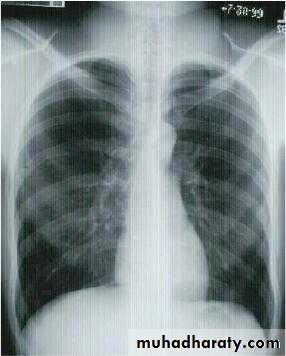

Investigations :-

1-Chest X-Ray2-CT chest